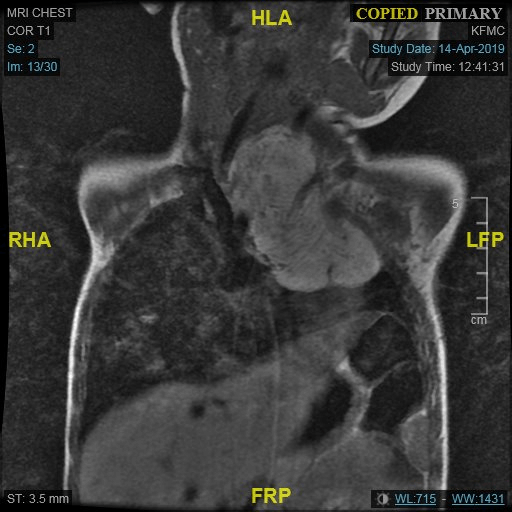

MRI was done to obtain more information about the relation between the mass and the vessels. It revealed lobular high intense tumor on both T1 and T2-weighted images equivalent to subcutaneous fat, no solid enhancing component with complete encasement of the LT common carotid and subclavian arteries and it is abutting the posterior aspect of the aortic arch (Figure 4).

Figure 4: MRI.